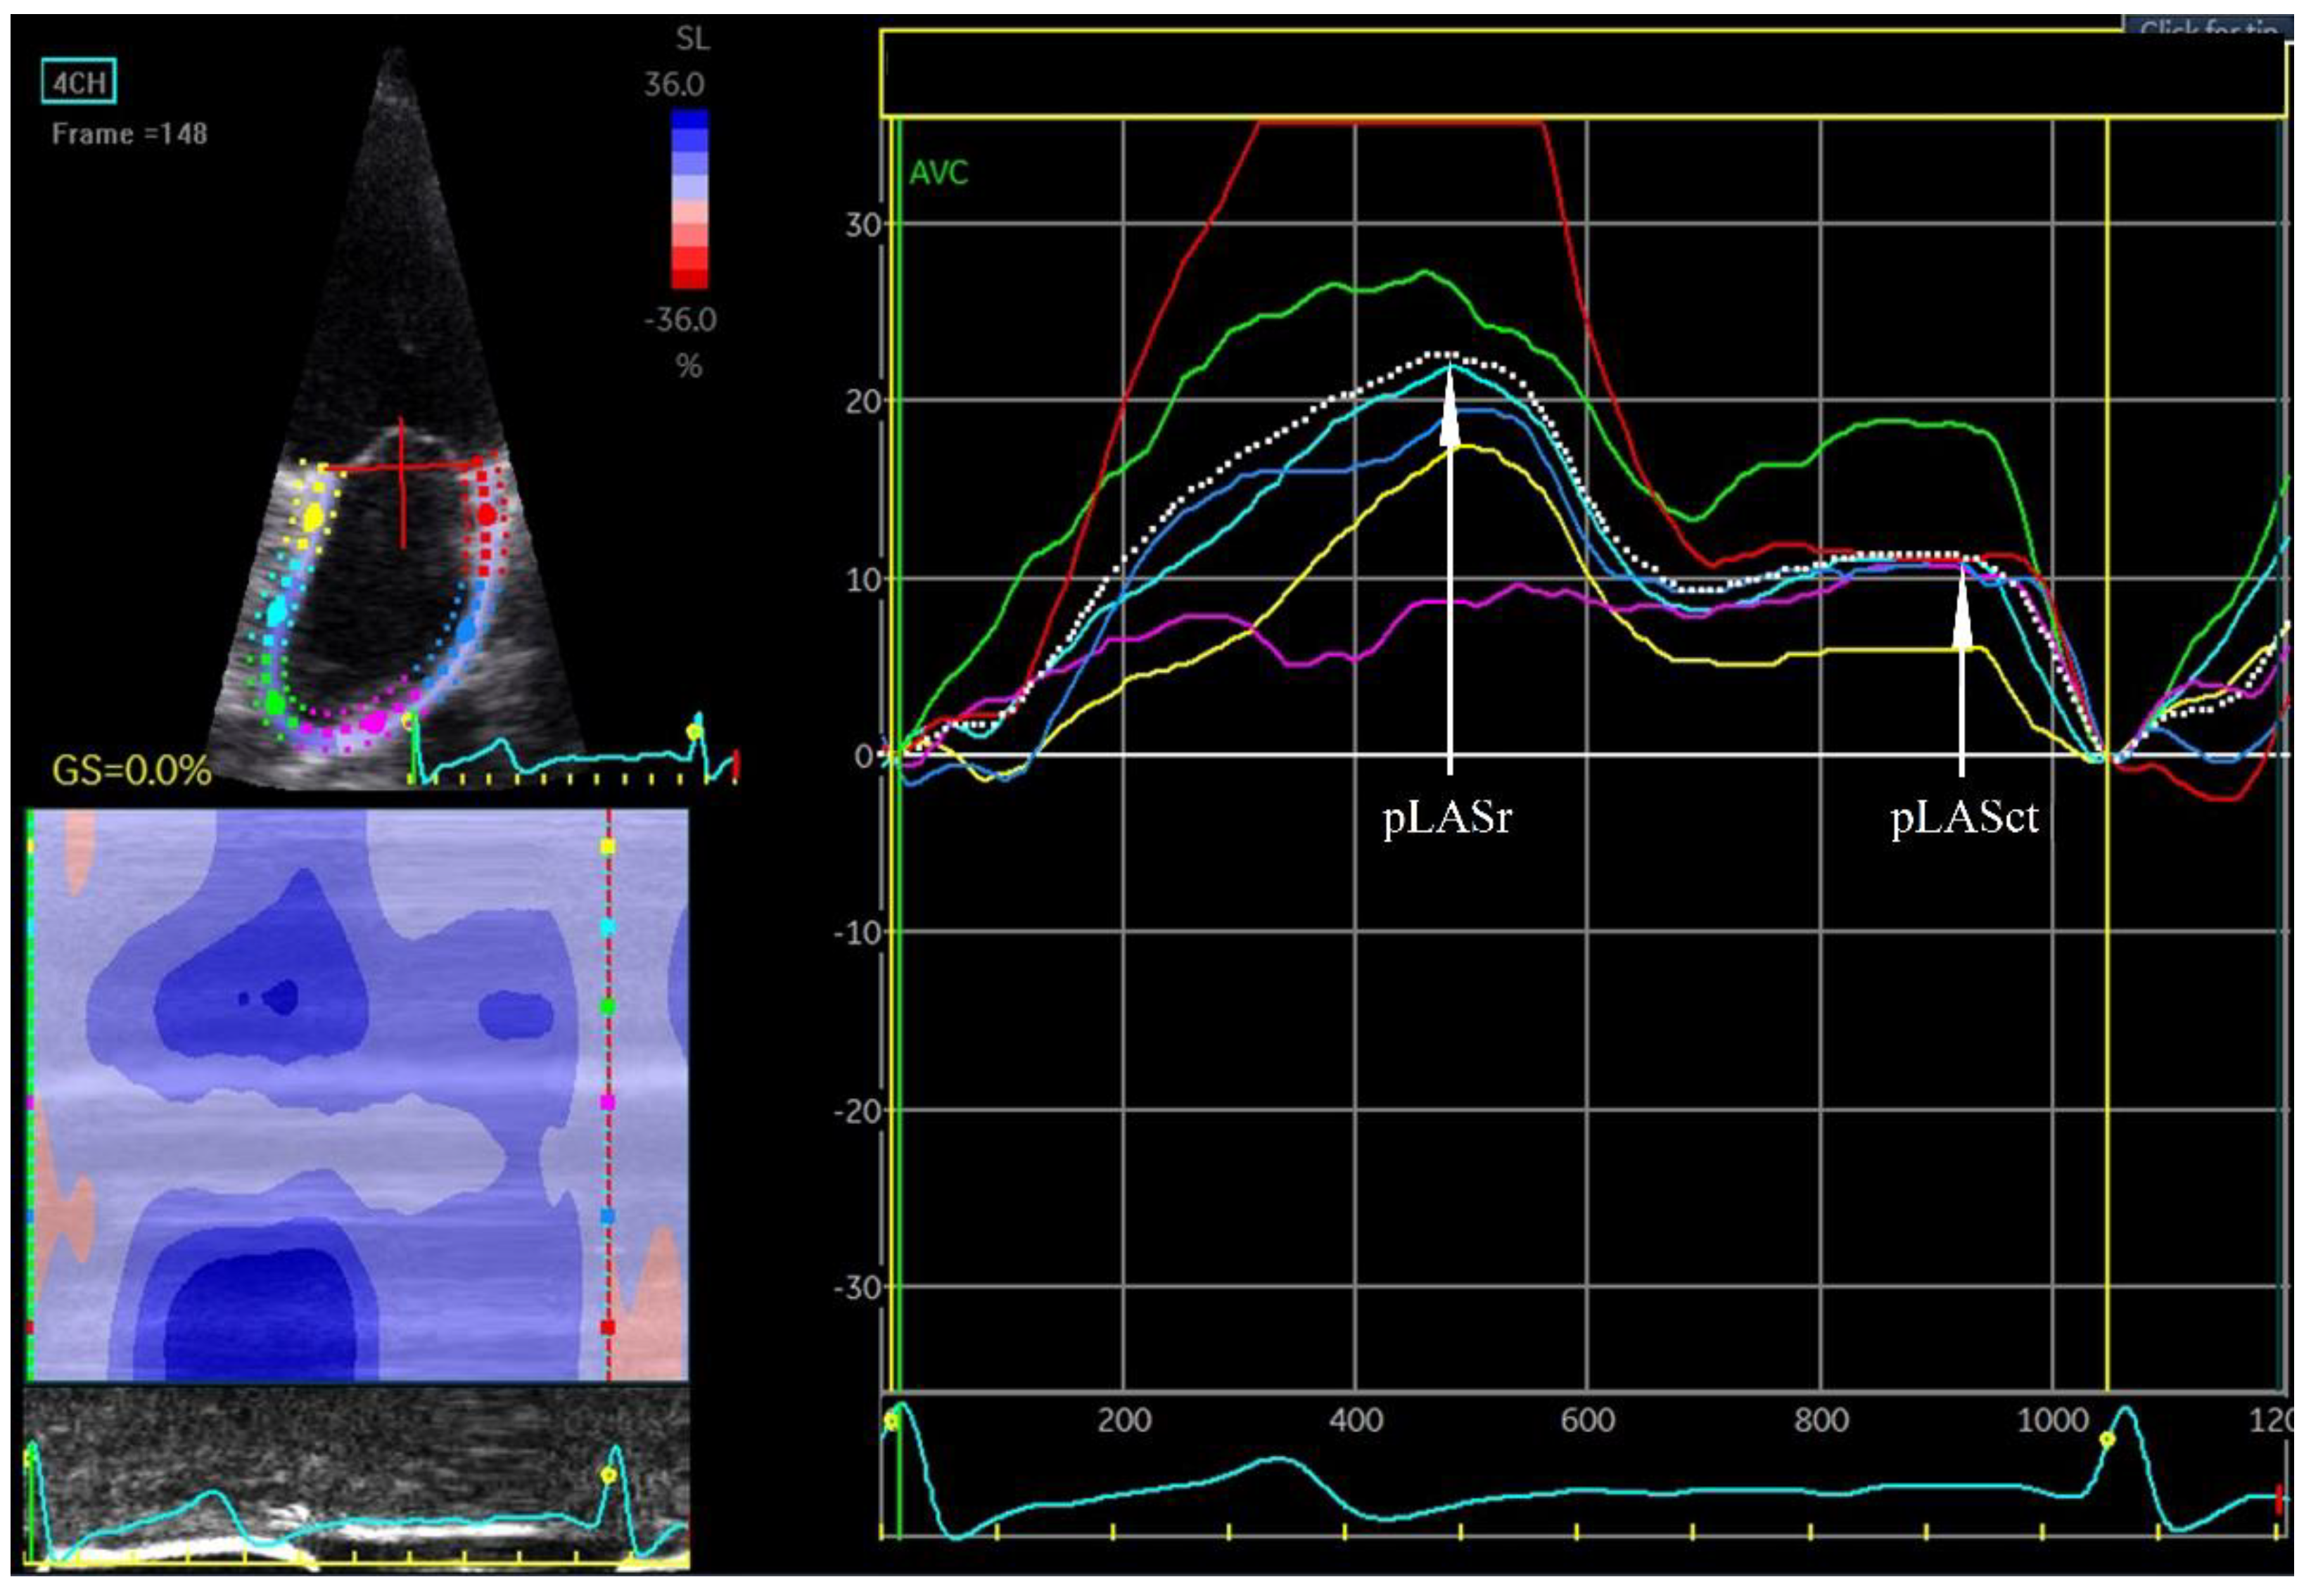

Figure 4. Left atrial strain. pLASr 22%, peak left atrial stain measured during the reservoir phase; pLASct 11%, peak left atrial stain measured during the contractile phase. The measurements are the average of the 6 assessed left atrial wall segments. The measurement was made in the apical four-chamber projection during sinus rhythm.